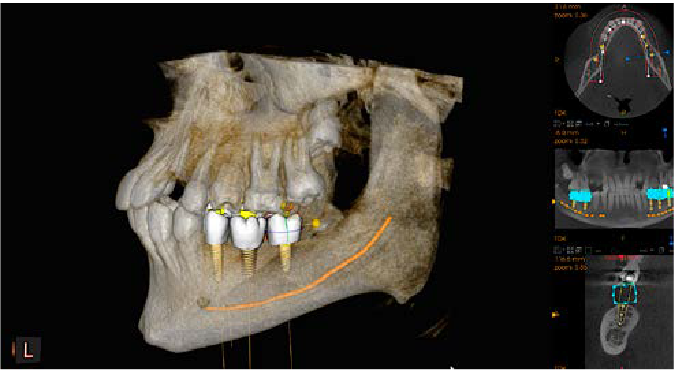

Implantes

Planifique los implantes con confianza gracias a nuestro avanzado software de planificación de implantes con coronas virtuales personalizadas y a la completa biblioteca de implantes